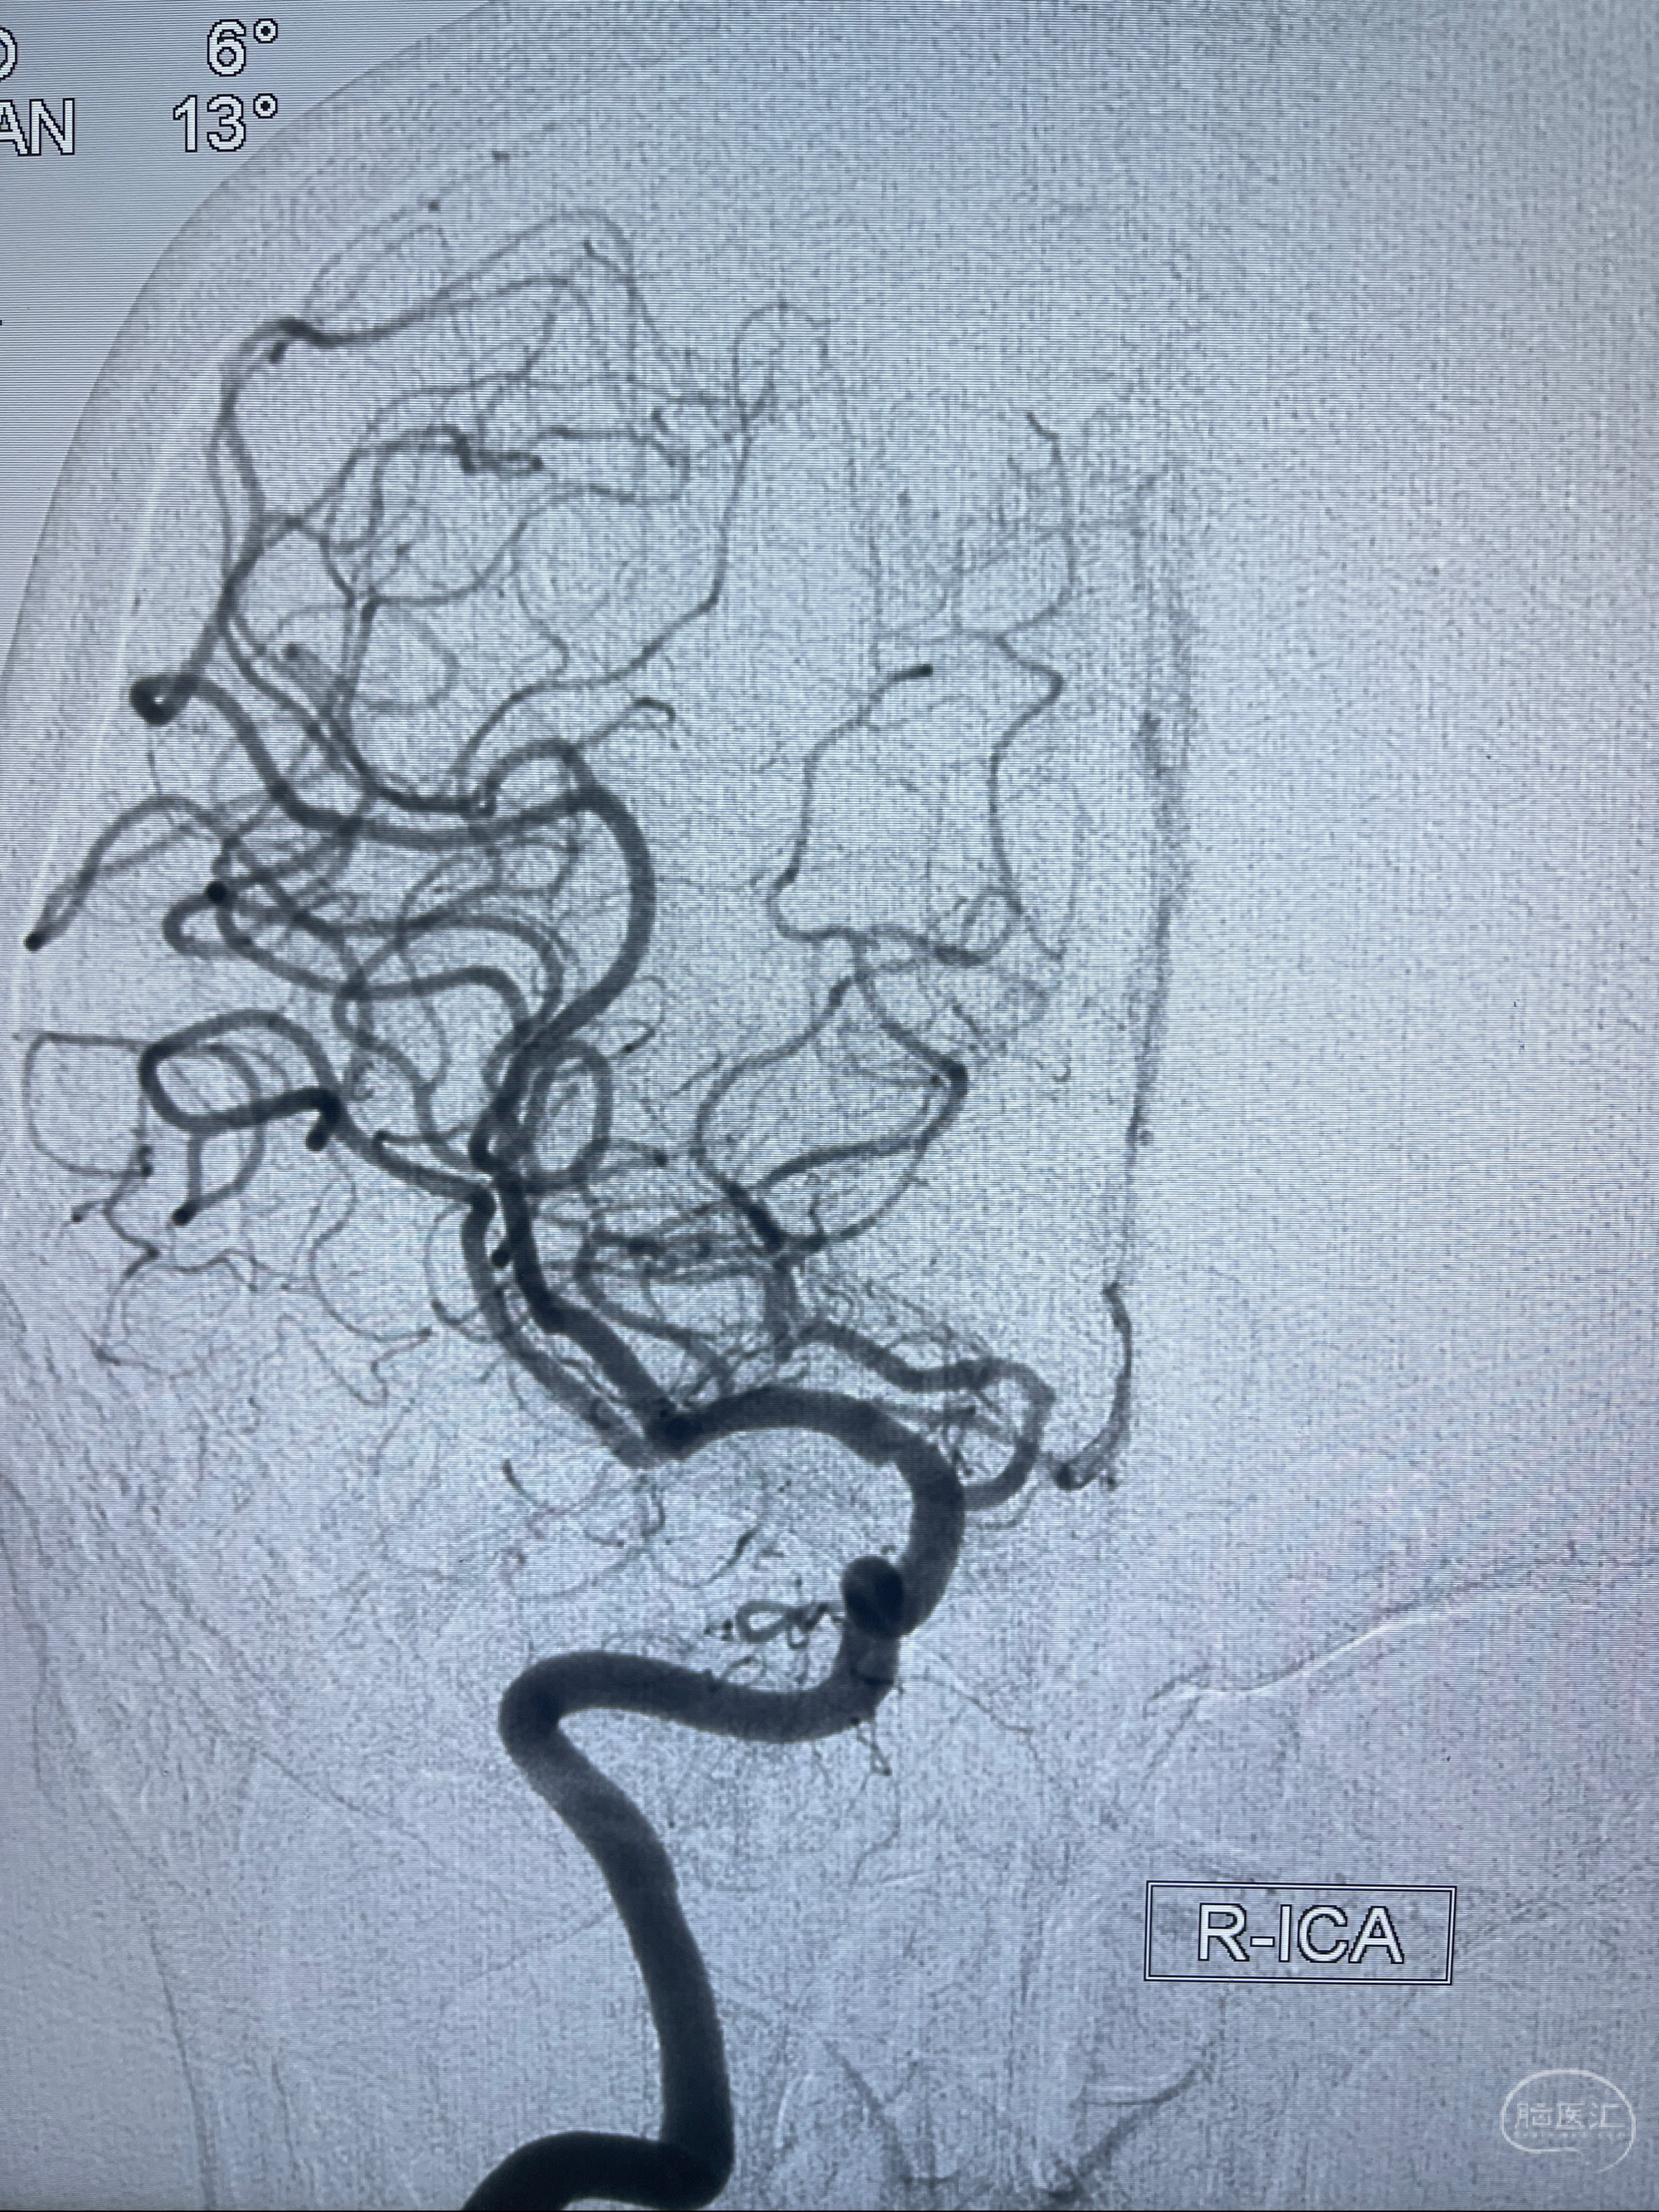

2023-02-02 沛县人民医院 头颅CTA:大脑动脉环发育变异,头颈部动脉粥样硬化,双侧颈内动脉及椎动脉颅内段多发狭窄;

2023-02-15DSA